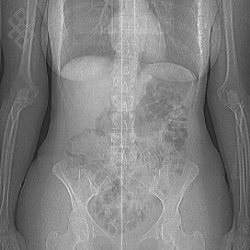

Scanner Corps Entier

Déroulement

La durée moyenne de l'examen est de 20 min.